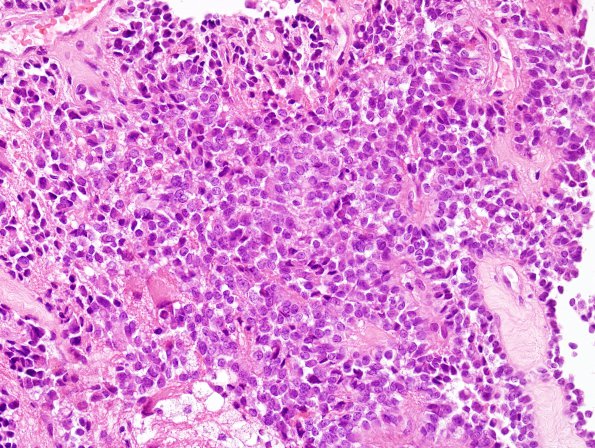

6B4 Papillary Tumor Pineal Region (Case 6) H&E 7

Higher magnification of the neoplasm (H&E)